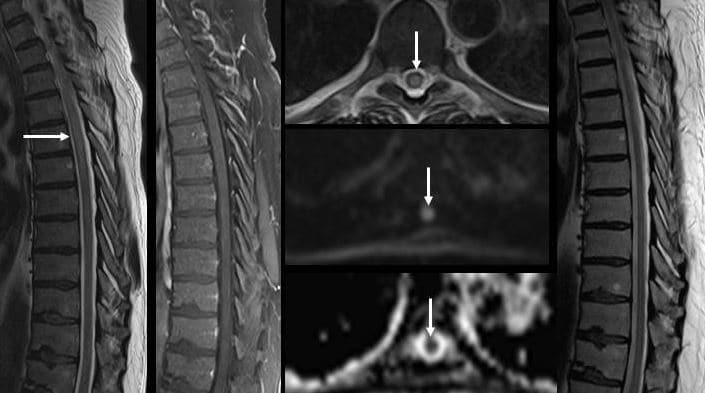

- МРТ. На миелит указывает отечность, размывание границы между белым и серым веществом. Обнаруживаются опухоли, гематомы.